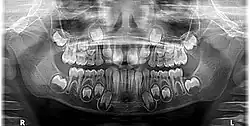

Radiographic appearance

On radiographs, enamel appears as the most radiopaque (white) structure due to its high mineral content.[19] Dentine and cementum are less radiopaque and are usually indistinguishable from each other.[19] The pulp chamber and root canals are radiolucent (dark), centrally located within the tooth structure. The periodontal ligament appears as a thin, radiolucent line between the root and the lamina dura.[19]

Figure 6: X-ray showing permanent dentition[20]